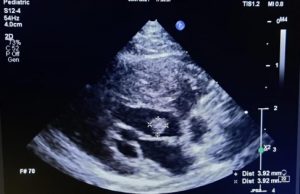

”Kesin tanı için bizden destek istediler. Görüntüleri incelediğimizde bunun nadir gözlenen bir tümör olabileceğini gördük. Olayı tanımladık ve bilim dünyasına kazandırdık. Kalp hastalıklarına her yaştaki kedi ve köpeklerde sıklıkla rastlanmaktadır. Kardiyak tümörlere ise kedilerde nadir rastlanır. Bu tümörlerin teşhisi genellikle ekokardiyografik muayene yani kalbin ultrasonografisiyle yapılır. Sunulan vakadaki ‘papillar fibroelastoma’ primer bir kalp tümörüdür ve iyi huylu olarak bilinir. Bununla birlikte, bu tip tümörler tromboemboli (pıhtı atma) riski taşır, felç ya da enfarktüs gibi komplikasyonlara sebebiyet verebilir. Bu tip olgulardaki belirtiler net değildir ve kitlenin boyutu veya yapısıyla bağlantılı olarak değişkenlik gösterebilir.”

Vakanın, bilimsel bir makaleye dönüştürüldüğünü dile getiren Prof. Dr. Civelek, ”Bu yayını hazırlamamızdaki amaç ise veteriner hekimliğin geldiği noktayı gözler önüne sermek ve bunun ötesinde konuyla ilgili meslektaşlarımıza referans teşkil edecek bir eser ortaya koymaktı. Yaptığımız araştırmalar sonucu bilim dünyasında kedilerde daha önce bildirilmiş bu tip bir fibroelastom vakasına rastlanmadığını gördük. Bu vakanın bir ilk olması da bizim için ayrıca sevindiricidir.” diye konuştu.